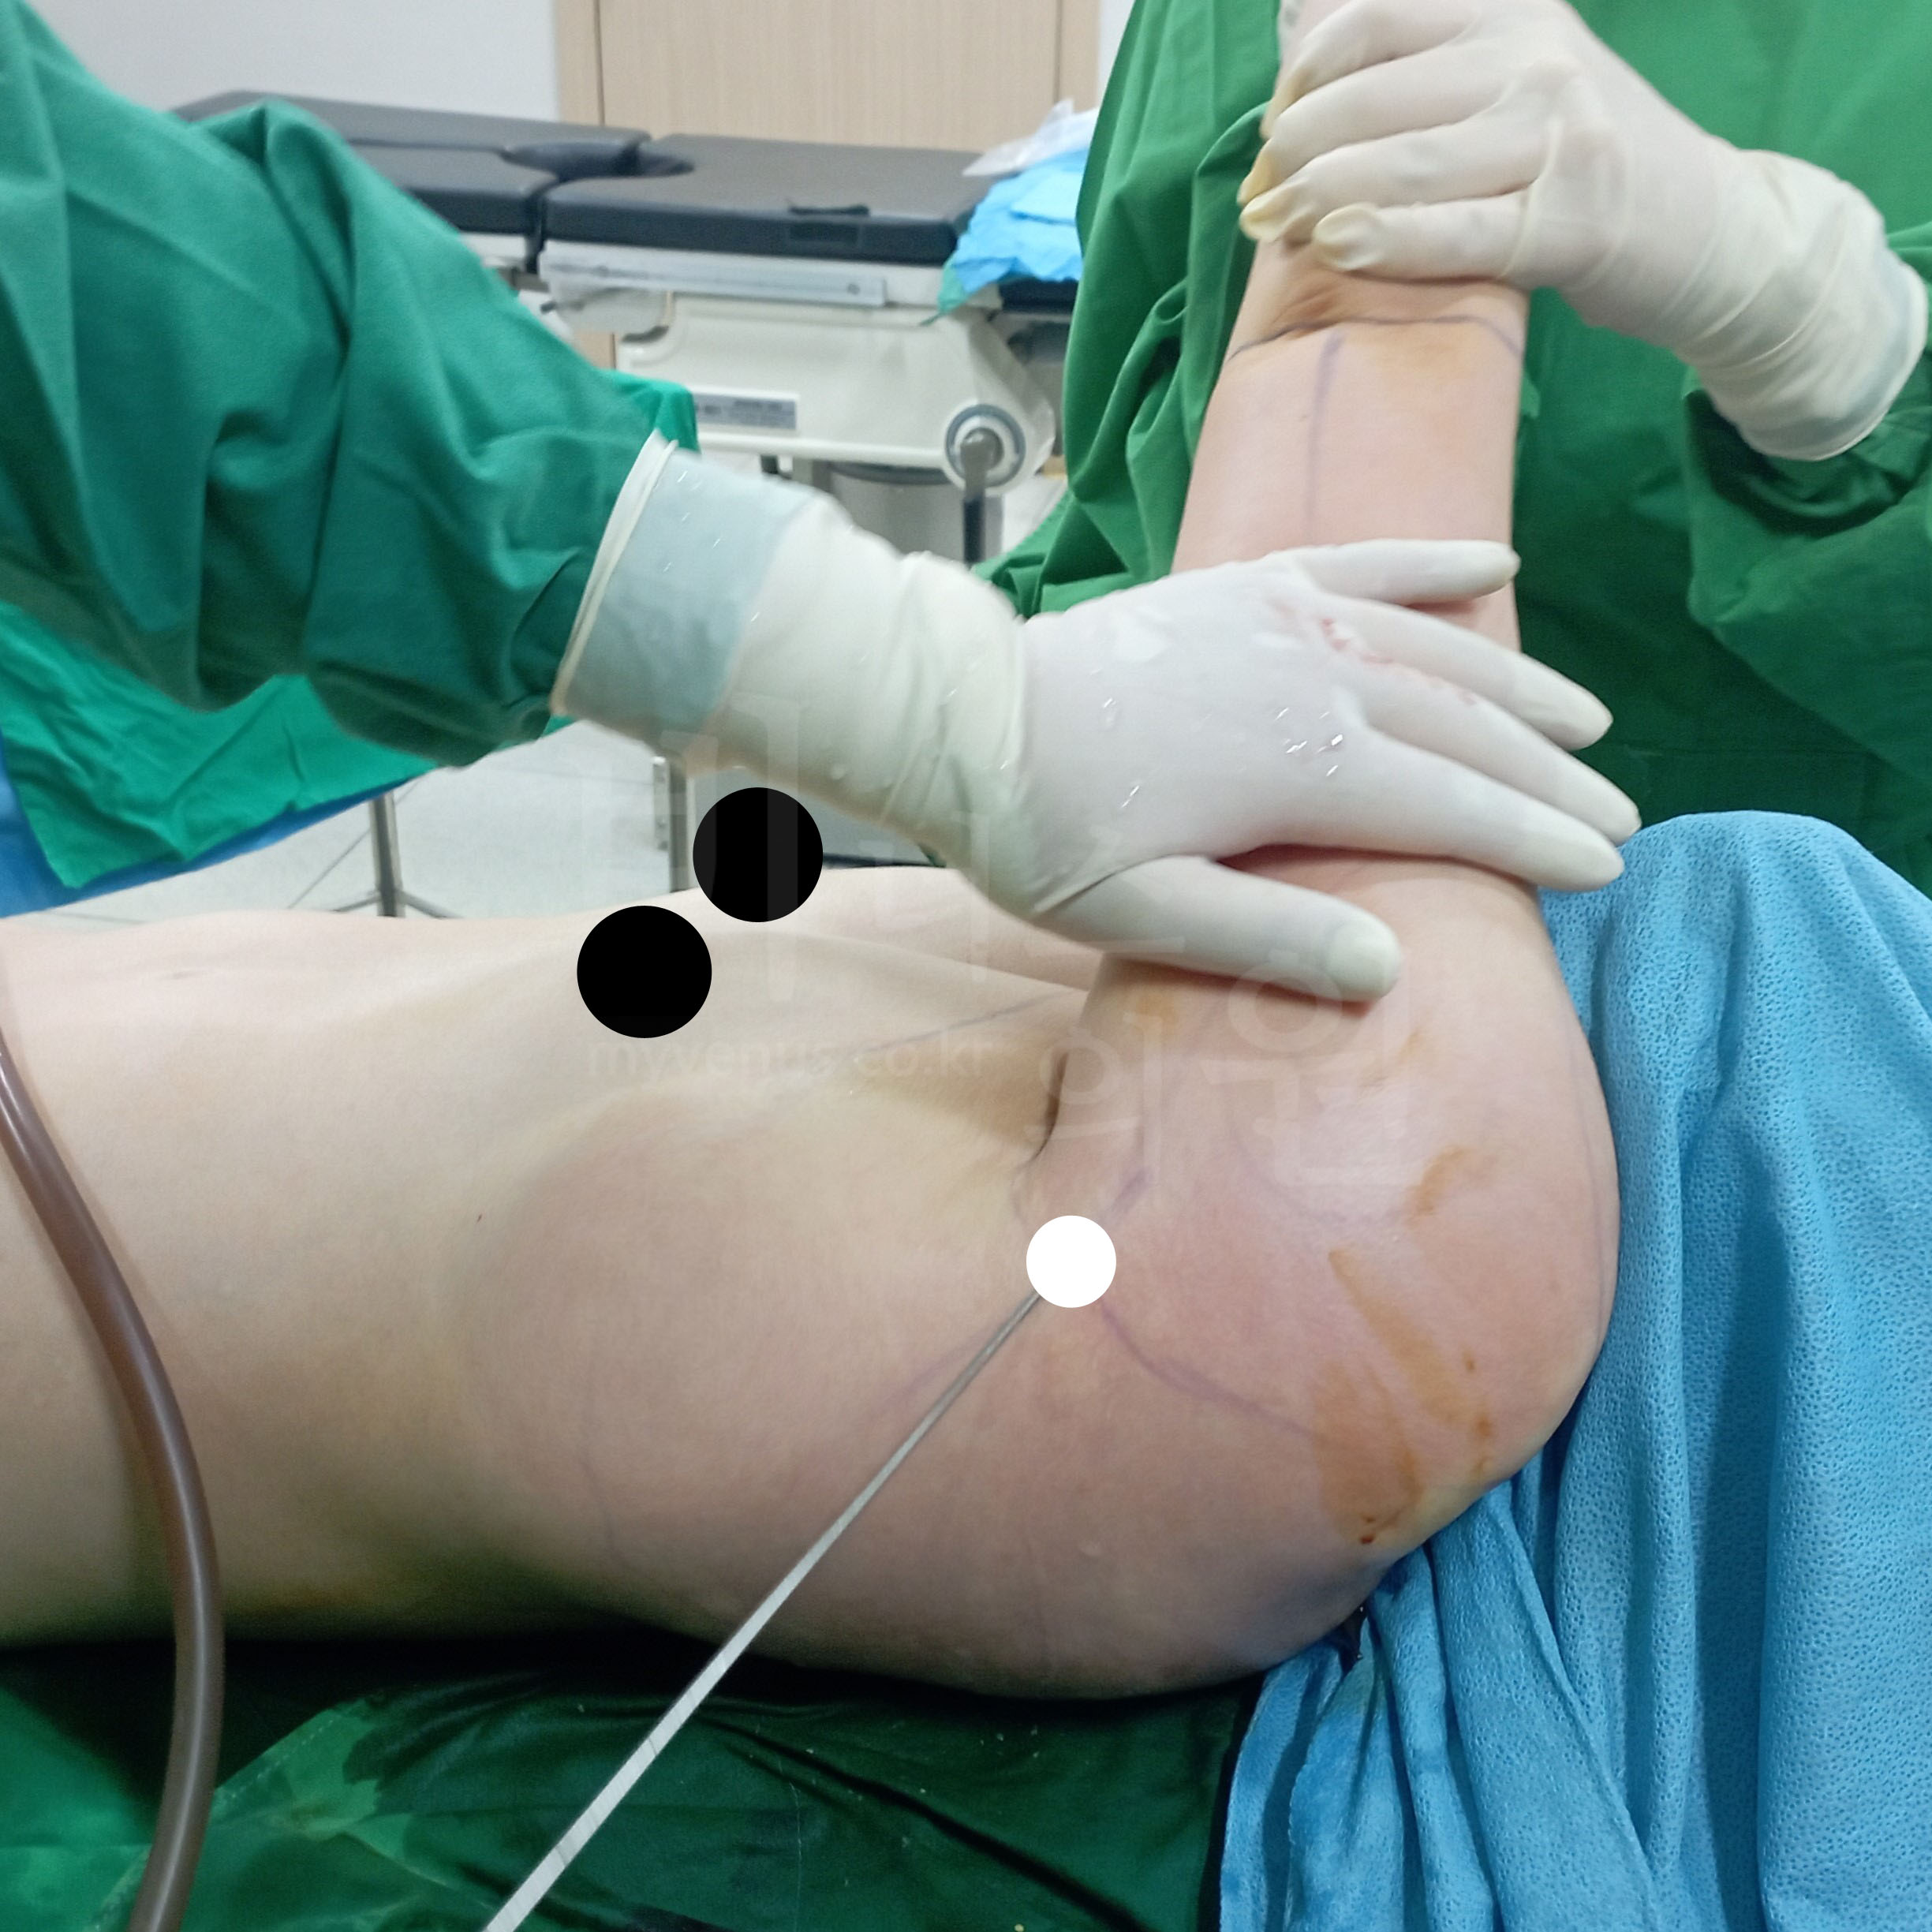

맞춤 투메슨트 용액으로 안전하게

붉게 부풀어오른 지방층, 효과적인 준비 과정

안전한 흡입을 위한 맞춤 투메슨트 주입

개인의 체형에 맞춰 투메슨트 용액을 팔뚝 지방층에 주입합니다. 지방이 익는 듯한 과정을 거치며 조직과 지방이 자연스럽게 분리되고, 이때 마이크로 흡입관을 이용해 지방만을 정교하게 제거합니다. 이 용액에는 국소마취제와 혈관수축제가 포함되어 있어 통증은 최소화되고, 출혈 없이 안전한 흡입이 가능합니다.